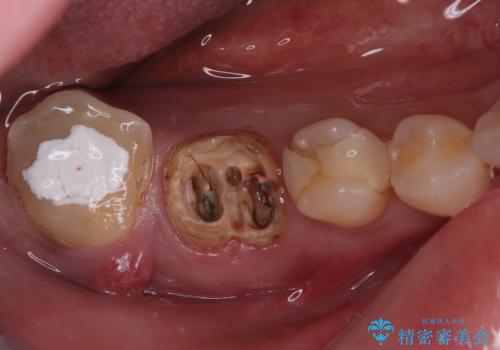

- 奥歯から膿が出てくることを気にして来院された患者様です。

診察より、奥から2番目の歯が割れている可能性が非常に高いため、まずは奥から2番目の歯の状態を診断することとしました。

クラウンを外したところ、目視でも確認できる破折線が認められたため、抜歯することとしました。